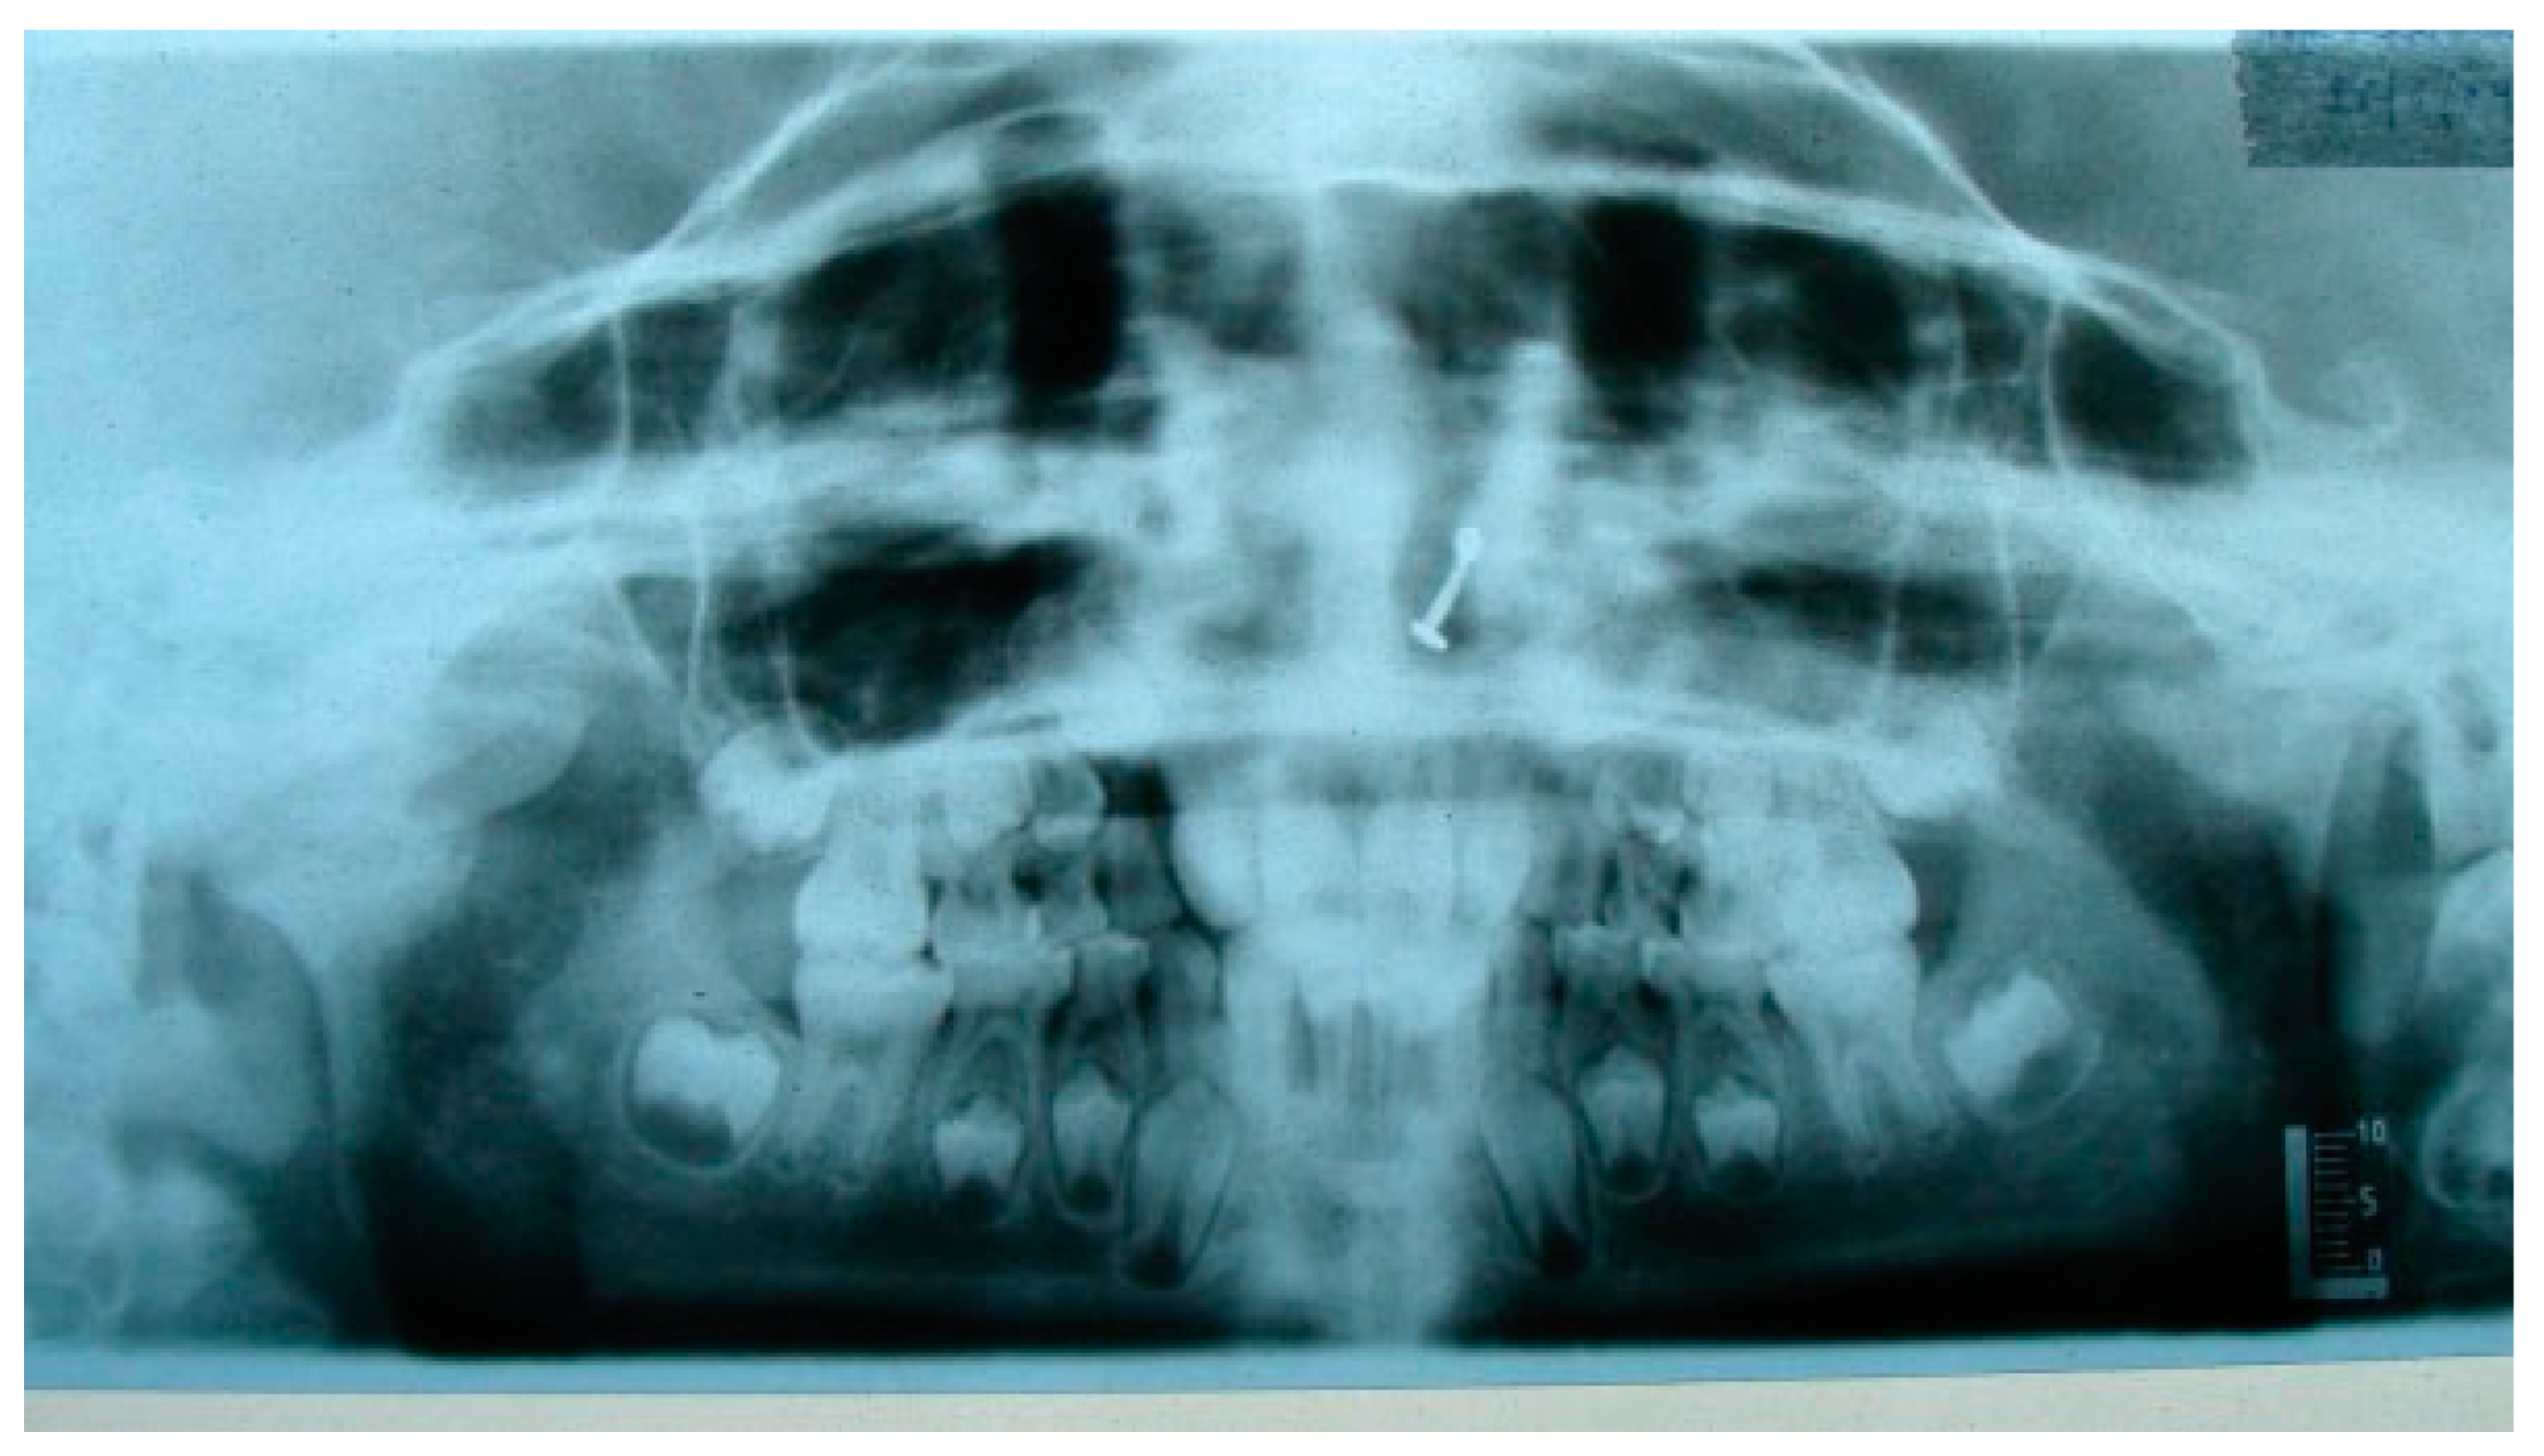

Figure 1. Preoperative OPG of right temporomandibular joint ankylosis.

Figure 2. Postoperative OPG at 6 years of follow-up (black arrow depicting CCG graft with temporalis muscle interpositioning with respect to right temporomandibular joint).

A retrospective study of post–ankylotic TMJ reconstruction of all the patients who underwent surgery for the TMJ ankylosis over a period of 11 years from 2002 to 2013, which were operated by the senior author (Y.B.), was undertaken to evaluate demographics, type of TMJ ankylosis, and modality of post–ankylotic TMJ reconstruction. The following inclusion criteria were considered for enrolling patients in this study: (1) history of traumatic injury to the face or jaws; (2) clinical and radiographic evidence of bony ankylosis at the time of presentation; (3) reconstruction of the TMJ using autogenous or alloplastic material after surgical release of ankylosis. Patients were assessed for (1) maximum interincisal opening pre and post operatively; (2) restored vertical ramal height; (3) occlusion; (4) facial symmetry; and (5) postoperative complications. Radiographic evaluation consisted of both preoperative and postoperative panoramic radiography Orthopentomogram (OPG) (Figure 1 and Figure 2) and CT scans in axial, coronal, and sagittal sections with three-dimensional reconstruction (Figure 3 and Figure 4). Surgical protocol was that the TMJ was approached through the Al-Kayat and Bramley’s incision and at least 2 to 2.5 cm resection of the ankylotic chunk was performed in all our cases. Ipsilateral and contralateral coronoidectomy was performed when required to achieve passive mouth opening. Interpositional arthroplasty was done using various materials such as temporalis fascia, temporalis muscle, and articular disc, whereas joint reconstruction was done using CCG and titanium reconstruction plate with condylar head. Intensive physiotherapy postoperatively was an integral part of protocol.

The unique ability of the CCG to remodel into neocondyle could be well appreciated on the digital OPG and CT scan of the patient. The length and width of the neocondyle was very much comparable to the length of the condyle on the unaffected side at 6 years follow-up. Thus, the neocondyle formed using the costochondral cartilage was identical to the unaffected mandibular condyle both structurally and functionally. Poor socioeconomic conditions and lack of awareness coupled with poor primary health care facilities lead many of these unfortunate patients to live with this debilitating condition well into adulthood. Five such adult patients with age ranging from 17 to 36 years reported to us for treatment of TMJ ankylosis. In all these patients, ankylotic bony mass extends beyond the boundaries of the joint capsule. Alloplastic reconstruction after the release of ankylosis was our method of treatment, although high cost of condylar prosthesis led us to use 2.4 mm condylar head reconstruction plate along with temporalis muscle interpositioning in these patients. Interpositional grafts may fail to restore the ramal height in bilaterally ankylosed adult patients, so alloplastic condylar reconstruction may become the preferred choice. Advantages of alloplastic TMJ reconstruction are that the physical therapy can begin immediately, there is no need for a secondary donor site, surgery time is decreased, and alloplasts can be constructed in such a way as to mimic the normal anatomic contours of the structures they are to replace [17,18]. Wolford and Karras have suggested autologous fat transplantation as a useful adjunct to prosthetic TMJ reconstruction, as it minimizes the occurrence of excessive joint fibrosis, heterotopic calcification, and improves the range of motion [19]. However, they have categorically stated in their discussion that heterotopic bone formation is seen in multiple operated joints and joints with previously failed alloplastic implants. Another method to combat heterotopic bone formation is the use of 10 Gy of irradiation in five fractionated daily doses in the immediate postoperative period [20]. In our series, none of the patients reported with heterotopic bone formation possibly because they had undergone a single surgical procedure for managing TMJ ankylosis. The risk of fossa perforation could have been taken care by interpositioning of temporalis muscle in all these patients.